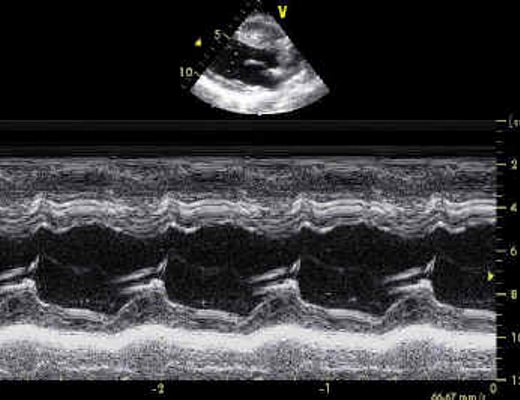

Da mercoledì primo maggio è attivo, presso la Cardiologia UTIC dell’Ospedale “Santa Maria della Speranza” di Battipaglia, il nuovo ambulatorio di ecocardiografia neonatale per screening cardiopatie congenite.

L’ambulatorio, coordinato dal dott. Marco Carbonella, dirigente medico dell’Unità Operativa di Cardiologia UTIC, si occuperà di visite cardiologiche ed ecografie pediatriche dedicate a pazienti fino a due anni di età.

Le cardiopatie congenite interessano l’1 per cento dei nuovi nati e risultano sotto diagnosticate durante le valutazioni routinarie anche per le difficoltà legate all’accesso alle indagini di secondo livello (ecocardiografia).

Le accresciute possibilità terapeutiche hanno contribuito a ridurre la mortalità infantile anche per le cardiopatie congenite neonatali particolarmente complesse; il 30 per cento di tale patologia viene diagnosticata dopo le dimissioni del neonato esponendo quest’ultimo a rischi aggiuntivi.